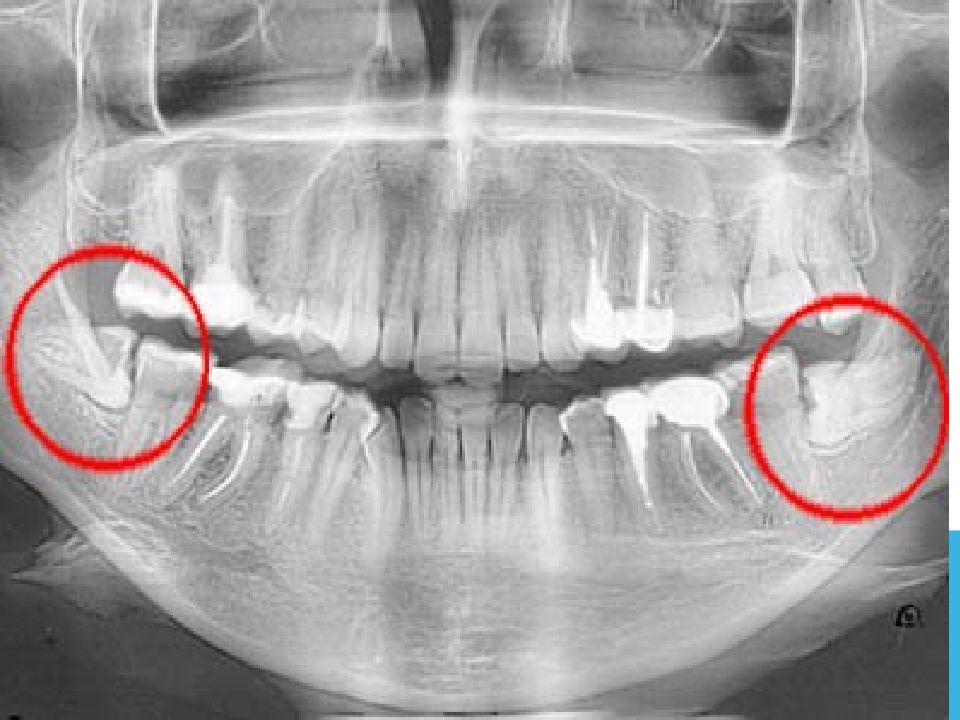

• Ортопантомография — полуретенция, дистопия зуба 3.8

Слайд 23: Ортопантомография — полуретенция, дистопия зуба 3.8